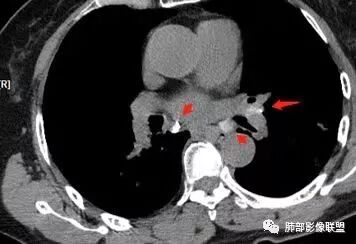

这是老问题:1、肺门区软组织密度影较弥漫;我们常规鉴别的就是结核?鳞癌?既往我们群里基本这两方向。2、弥漫的淋巴结钙化,加上马赛克灌注。马赛克灌注的原因是两个,一个是肺动脉的,一个就是小气道的问题。我们看增强的区域,没有看到栓塞,所以我倾向于小气道的问题,就是弥漫气道病变,慢性气道病变要考虑。我怀疑有没有淀粉样变性累及气道壁改变的可能。淀粉样变性是一个继发性病变,结核也可以,粉尘也可以。

这个病例支气管狭窄后扩张,肺门区有很多钙化的淋巴结,两肺弥漫的马赛克灌注,肺门淋巴结这么多,一个结核,一个尘肺,然后就是一个淀粉样变性,这几种最常见。鳞癌因为老年女性,除非吸烟,不太考虑,又不能绝对排除,所以就把鳞癌放到后。

今天这个病例有个明显的支气管狭窄,我倾向炎性,主要是和钙化淋巴结相关的,可能是继发的淀粉样变性。到底是什么感染,结核还是其他。我想看看复查后这个淋巴结,有没有突入到支气管腔内,如果有,他是继发于炎症的(比如中叶综合征,就是周围淋巴结压迫支气管,因为钙化淋巴结比较硬,支气管壁扛不住压力,突入支气管腔内,导致管腔狭窄,我们也称为结石征),如果没有,就和淋巴结关系不密切。之前有一例淀粉样变性的,淋巴结弥漫钙化,一种罕见的浆细胞型的CD。